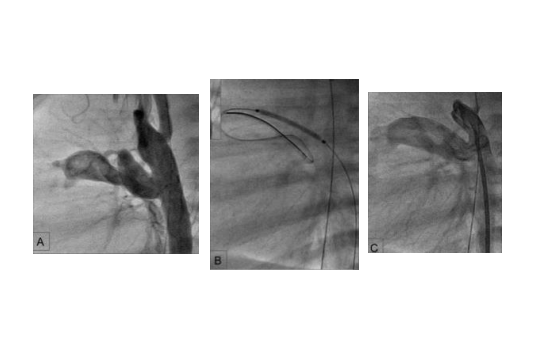

Angiography of a severely narrowed ductus arteriosus (A) into which a stent has been inserted on a balloon catheter (B). After stent deployment, an unimpeded outflow of contrast medium from the aorta into the pulmonary artery can be seen (C).